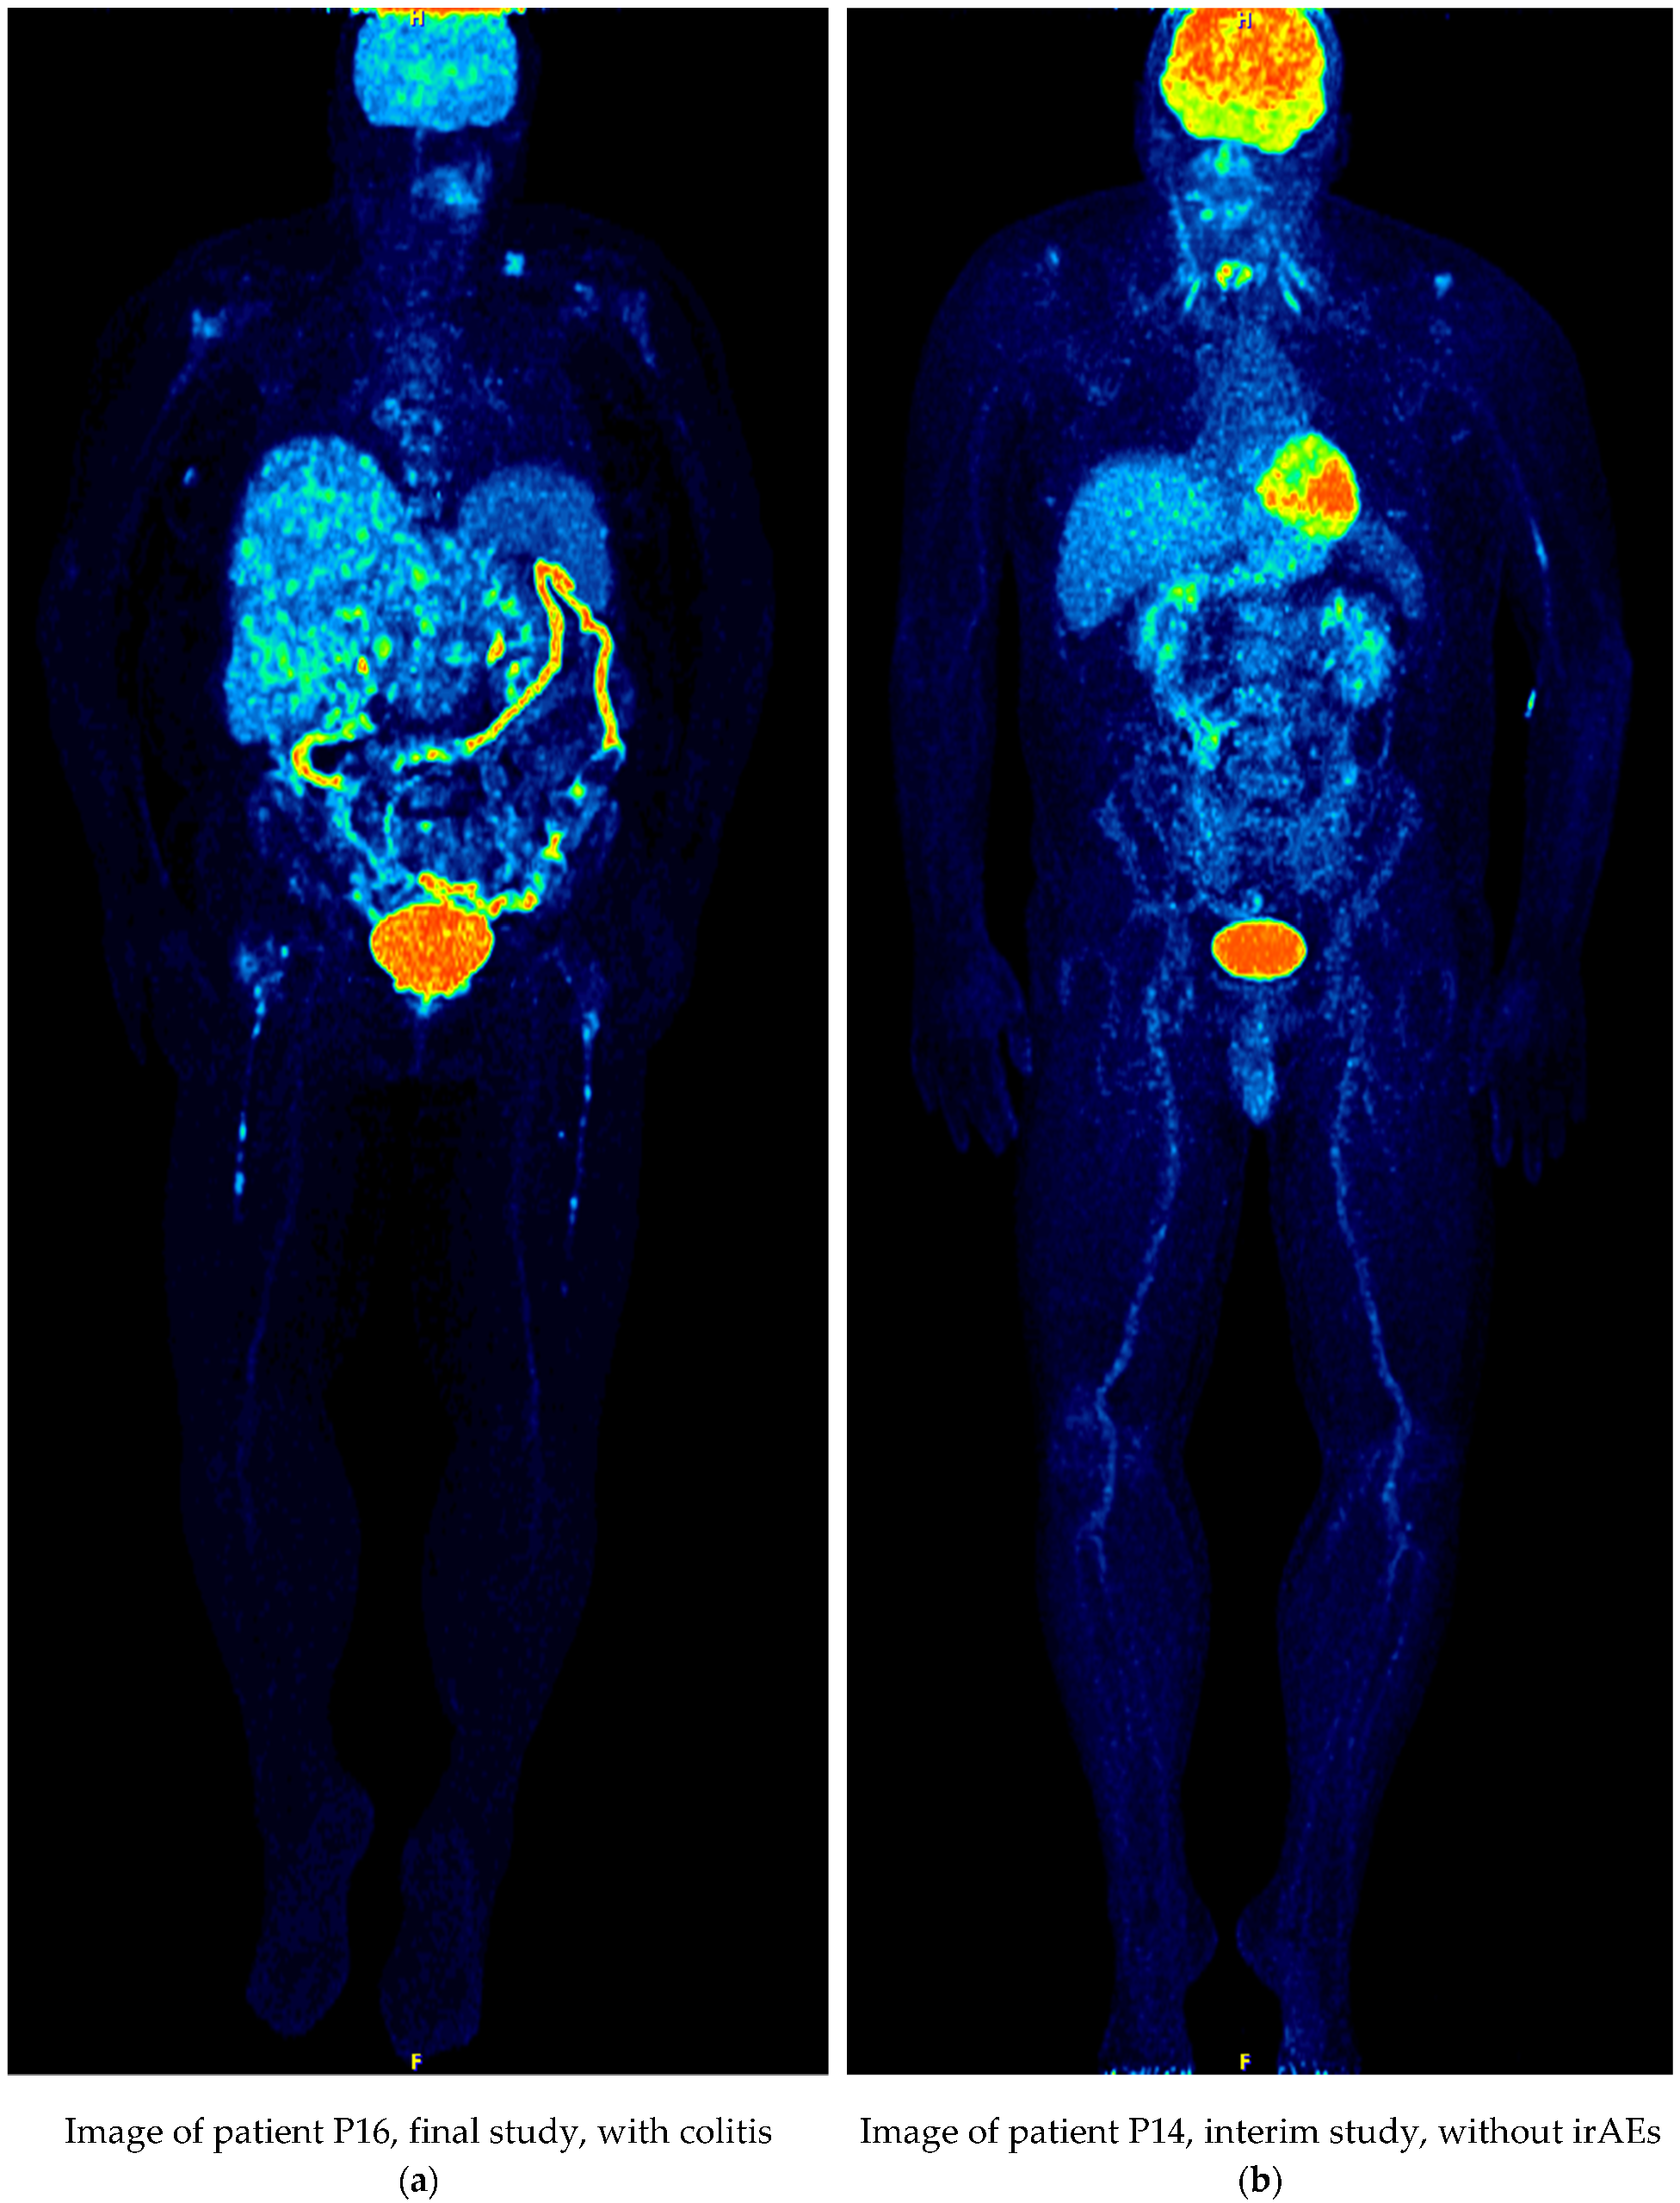

| P16 | 71/F | Baseline | Ipilimumab/Nivolumab | colon uptake | |

| Interim | colitis, sarcoid-like mediastinal lymphadenopathy | PMD | |||

| Final | colitis | PMD | |||

| P16 | Baseline | 2.398 | colon uptake | ||

| Interim | 2.511 | colitis, sarcoid-like mediastinal lymphadenopathy | PMD | NO | |

| Final | 2.574 | colitis | PMD | NO | |

| P16 | Baseline | 2.155 | colon uptake | ||

| Interim | 2.261/0.106 | colitis, sarcoid-like mediastinal lymphadenopathy | PMD | NO | |

| Final | 2.378/0.223 | colitis | PMD | NO | |